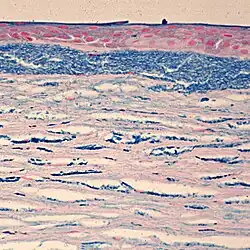

Colloidal iron staining shows deposition of glycosaminoglycans in the cornea

Macular Corneal Dystrophy is an autosomal recessive genetic disorder caused by mutations in the carbohydrate sulfotransferase gene (CHST6), resulting in abnormal proteoglycan synthesis. The accumulation of abnormal glycosaminoglycans in the corneal epithelium and stroma leads to progressive opacification of the cornea and subsequent loss of visual acuity.[7][8] There are three variants of MCD characterized by immunophenotype:

Histopathological staining shows characteristic alcian blue-positive deposits.[7] Various imaging modalities, including confocal microscopy and ocular coherence tomography, can provide information about the changes within the cornea and may be suitable replacements for tissue biopsy and excision.[8]